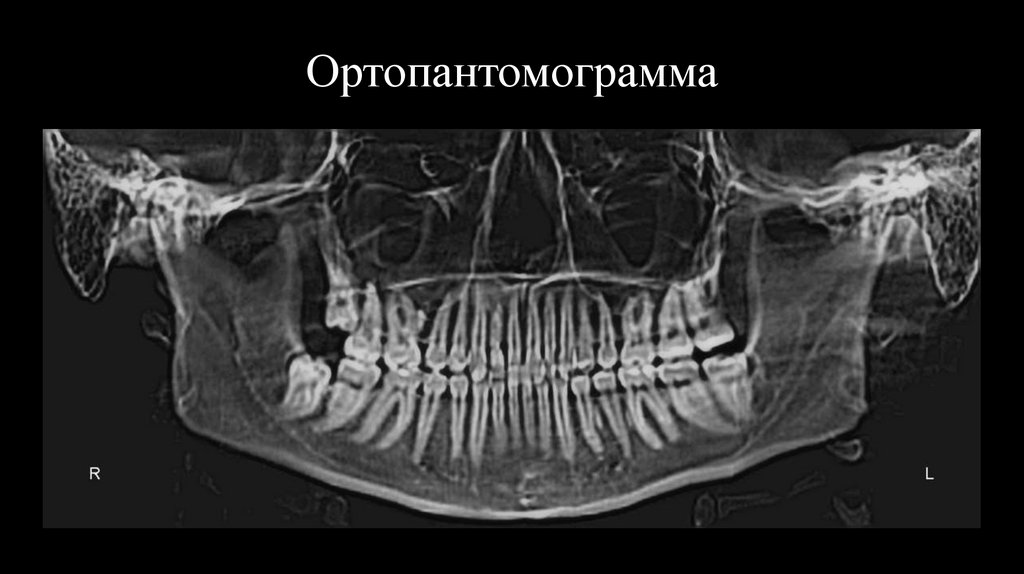

Penn анализ

13. Ортопантомограмма

14.